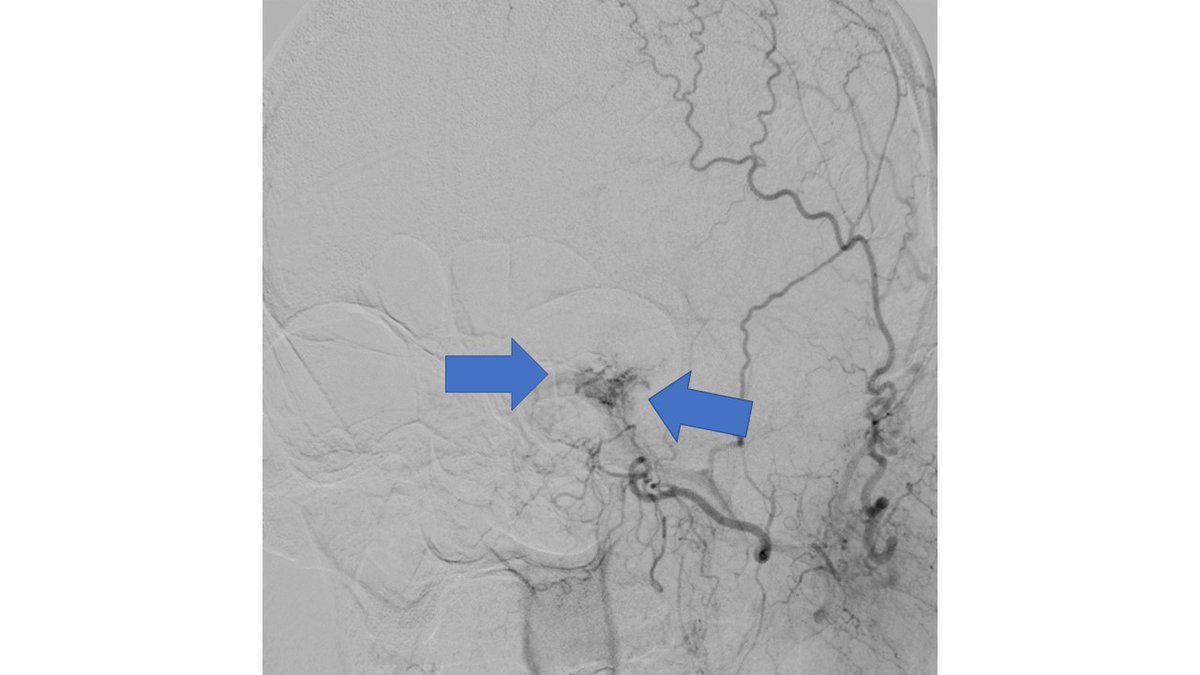

MRV shows left Transverse and sigmoid sinus thrombosis. No improvement after 2 days of IV heparin. Pt requires heavy sedation, ventilation for headache/agitation.

DSA also confirmed the extensive clot. In view of her recent LSCS 20 days ago, we were hesitant about giving IV lytics (urokinase infusion). Hence went in with an ACE 5 Max catheter and sucked out a mountain of clot